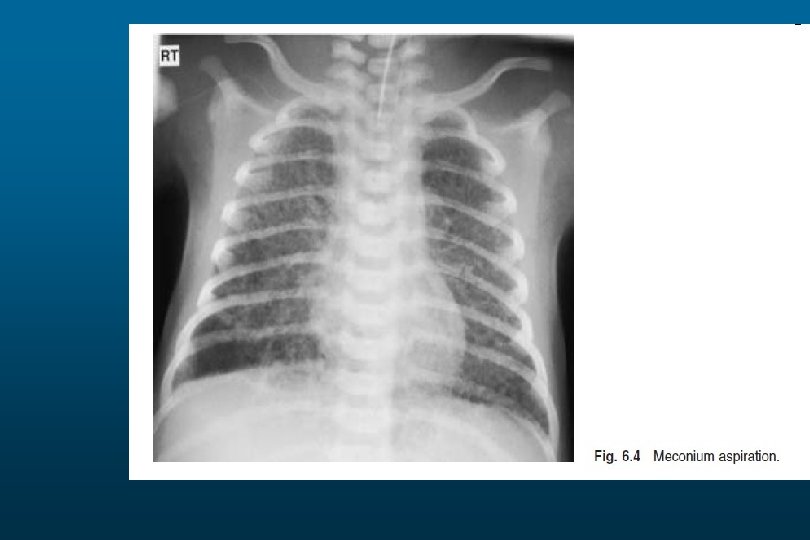

RDS